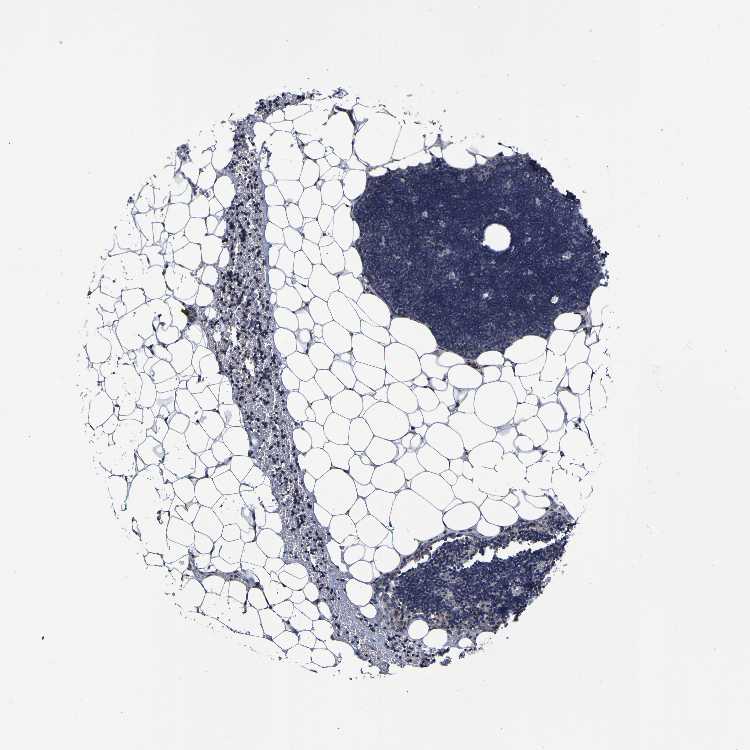

TISSUE PRIMARY DATA LYMPH NODE Show tissue menu

Lymph node

Tissue proteome

Lymphoid tissue

LYMPH NODE - Expression summary

Protein expression

Lymph nodei

On the top, protein expression in current human tissue, based on all annotated cell types, is reported with the units not detected (n), low (l), medium (m) and high (h). Underneath, protein expression in each annotated cell type are reported using the same units.

Protein expression data is based on knowledge-based annotation. For genes where more than one antibody has been used, a collective score is set.

If knowledge-based annotation could not be performed for a gene, no data is displayed here. View antibody staining data further down this page.

LYMPH NODE - Antibody stainingi

Antibody staining in the annotated cell types in the current human tissue is reported as not detected, low, medium, or high, based on conventional immunohistochemistry profiling in selected tissues. This score is based on the combination of the staining intensity and fraction of stained cells.

Each image is clickable and will lead to virtual microscopy that enables deeper exploration of all samples and also displays staining intensity scores, fraction scores and subcellular localization as well as patient and tissue information for each sample.

Antibody HPA012113Antibody HPA016980

Germinal center cells LowNot detected

Non-germinal center cells LowNot detected